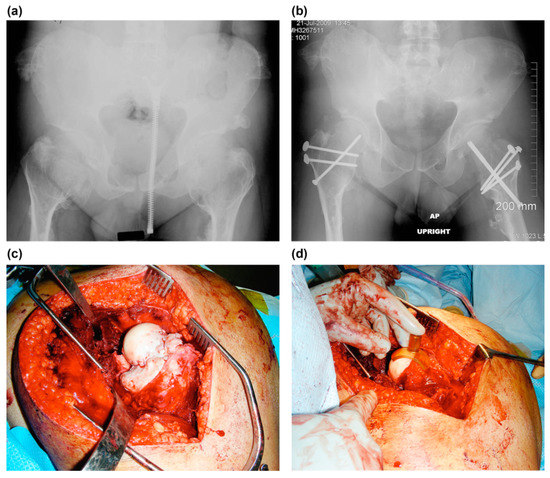

Figure 4.

The case of a 22-year-old man with symptomatic bilateral femoroacetabular impingement in MHE (case no. 6). (a) A preoperative anteroposterior radiograph of the hip shows a large bump at the medial side of the femoral neck and severe coxa valga. (b) Postoperative anteroposterior radiograph of the hip. Valgus intertrochanteric osteotomies were performed on both hips using blade plates, and the trochanteric osteotomy sites were fixed with 3.5 mm cortical screws.